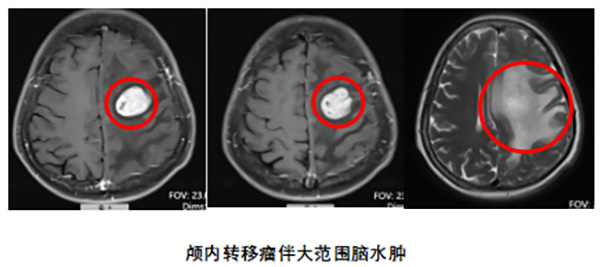

六年抗癌陷入僵局,脑转移雪上加霜

近日,我院神经外科接诊一位曾明确诊断为肺腺癌并与之抗争六年之久的老年患者,初期的分子病理检查未能找到有效的靶向药物,她只能接受常规的放疗和化疗。当病情进展、化疗耐药后,二线免疫治疗的效果仍不理想。更严峻的是,最近1个月,她出现了脑部转移,导致右侧肢体乏力、活动笨拙,并伴有难以完全用脑转移解释的四肢麻木。患者与家属感到前路迷茫,陷入深深的焦虑与无助。

神经外科迅速启动了多学科诊疗(MDT)模式。神经外科、麻醉科、肿瘤血液科、重症监护室(SICU)等专家共同制定了周全的个体化方案。手术顺利完整切除了脑转移灶。病理科主任王红梅第一时间确认肿瘤来源于肺部,为后续精准检测铺平道路。术后,患者不仅顺利康复,其右侧肢体乏力和四肢麻木的症状也逐渐好转,生活质量得到有效提升。